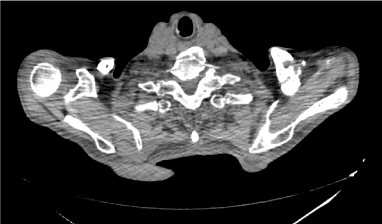

He was previously investigated before admission with a chest radiography, which came back normal. A barium swallow (Figures 1 and 2) was performed, which showed narrowing of the upper esophagus and gastro-esophageal reflux of contrast. An upper digestive endoscopy (UDE) found a tortuous esophagus presenting tertiary waves. An esophageal manometry was not able to be performed due to difficulty of catheter progression.

Figure 1. Barium Swallow: Esophageal Narrowing.